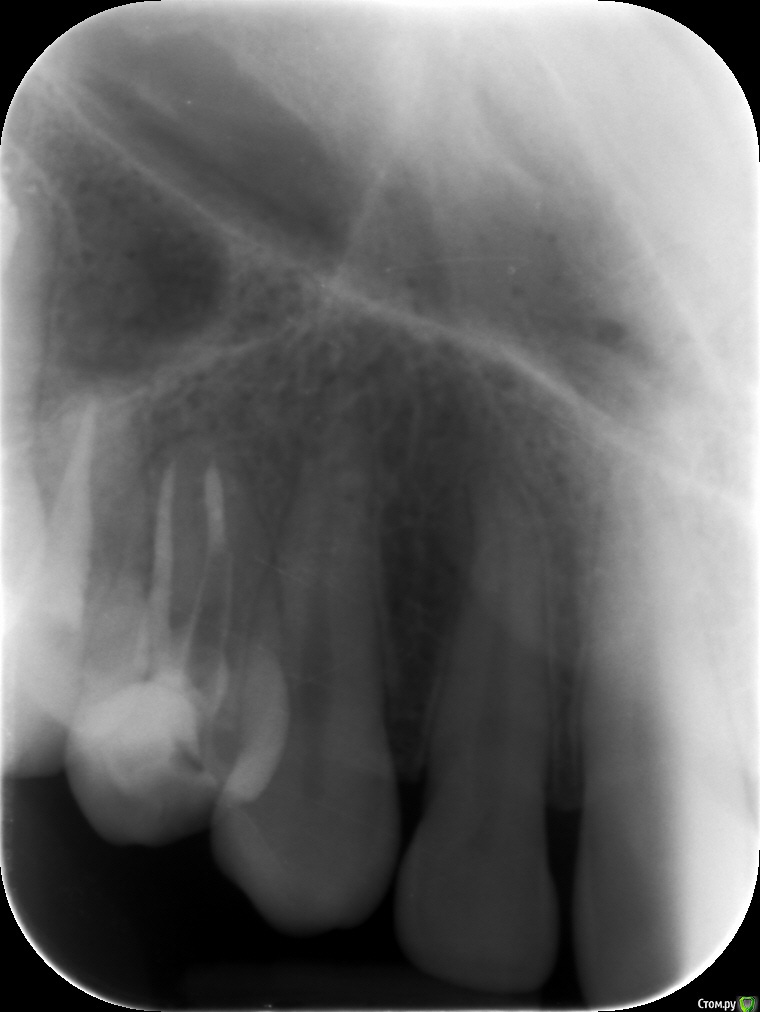

Здравствуйте. Подскажите пожалуйста,как выглядят зубы после лечения? Было две кисты .как правильно считать зубы не знаю.верхние правые 4 и 6

post-49942-0-02902700-1526574729_thumb.jpg